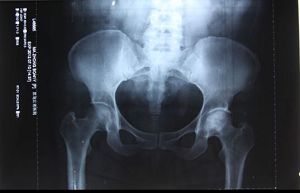

马忠波在北方股骨头坏死研究所的诊断

二零零零年三月,我到哈尔滨北方股骨头坏死研究所,我要取回我的病历和当时拍的CT片。我见到了曾给我看过病的研究所所长,见我走進来他们很震惊:你不是那个双侧股骨头坏死二期,在地上爬的那个患者吗?我说是啊。他惊讶的说:“你能走了?”我说:“你看我这不是走着来的吗”!张医生说:你走一个我看看?他忘了我是走着進去的。我就在屋里再给他走,我说我在家啥都能干了,我盖房子,打工什么都能干。他问我我就乐,他说搞的什么名堂快说说。张医生马上查找我的病历,一看只拿了一副药,就说:“你这绝不是用药的结果,快说说你是怎么好的?”

张医生商量着我再拍一个片子,看看我的腿到底啥样了,我说我好了还花那个闲钱?医生说不要钱。

我说那我也不拍,好象我炼法轮功还不信任这个功法似的。屋里的几个病人听说我是背着来的,现在好了,都想看看我这股骨头恢复得如何。那些人也说:孩子你拍一个我们也看看啥样了。在大家的劝说下我拍了片子。拍完这个片子医生把最初来看病拍的那个片子拿出来对照,发现两个片子一模一样,大夫说你这腿也没好啊?看你这股骨头还跟烂土豆似的。看片子我的股骨头并没有变化,但我人却行动自如了。医生让我走、蹲给他们看,在我身上看不出股骨头坏死患者的任何症状,要不是张医生和片子作证,在场的所有医生和患者怎么会相信呢?我说这法轮功可神奇了,看你信不信,你信就有人管你。我说那片子有没有股骨头关我啥事呀,我能走我不疼就行呗,那我自己不疼我不知道啊。医生也说:对对,你不疼就行呗,管他片子啥样呢。

在事实面前,一个医生说:“法轮功确实能治病。”另一个说:“可不,要不咋有那么多人炼。”医生说:“既然法轮功能出这样的奇迹,电视里说法轮功能治病是骗人的,你为什么不站出来说句公道话。”我说:“我会的!”在这里我顺理成章的把原来拍的片子拿了出来。

1、哈尔滨北方股骨头坏死研究所

一九九九年二月六日我第一次去哈尔滨北方股骨头坏死研究所,也是最后一次在医院检查确诊,见到的就是所长,他是一个很正直很讲医德的医生。二零零零年三月份我去过他们研究所重新拍了一个片子,片子所展现的还是股骨头坏死,但是那次我是一个完全恢复了健康的人去拜访他的,他也奇怪,怎么片子没有变化,人却不一样了。当时在他身边的一位年轻的医生说:这个病例可以记录在我们研究所的历史上了,所长却说:那不行,这个患者的病不是我们治好的,她是炼法轮功好的,和我们的治疗没有一点关系。

那篇文章,黑龙江省公安厅的人也看到了,去研究所调查我的事是否属实,张连喜医生实话实说的讲述了他亲眼见证了大法的神奇。医生把我的病例号(一九九九年三号)和二零零零年三月份拍的片子对比着讲给他们,两次拍片的结果都写着“双侧股骨头坏死”,但是炼法轮功后人是个健康的人了。省公安厅的人在那里也明白了事实真相,这件事就不了了之了。

二零一二年我又一次去了哈尔滨北方股骨头坏死研究所取片,那位所长又给我拍了个片子,结果仍然是股骨头坏死的症状。

2、黑龙江省医院

我修炼后三天就把那么严重的股骨头坏死炼好了,我去了修炼前曾经看过病的省医院拍片,医学影像科的医生张明磊给我拍完片子,那个大夫就在X光检查报告单上确诊的“股骨头坏死”后面打了个问号,在诊断书的下面写着:“观察”两个字。但是他写出病例了,盖的章。他给我做各种检查我都正常,走道,蹲起都行,他很纳闷。我就问他,问号是啥意思?他说:你是股骨头坏死。你这不是好了吗?我说我们家人让我花钱来拍片,就想看看片子怎么样。片子是啥样呢就给写啥样,家人只想要片子。你这问号是啥意思,我到底是不是股骨头坏死?他说:是,是股骨头坏死。但是你哪都不疼,你不都正常了吗?他也不明白是怎么回事。他对我提出的问号很后悔,大夫的名章已经盖上了没有办法再改变了,也只好那样了,他一再说:是股骨头坏死,是股骨头坏死。

二零一二年七月十号在黑龙江省医院检查股骨头坏死的诊断。

3、阿城区医院

二零零五年我在砖厂干活时,偶尔碰到一个当地的医生,他早听说了我的事,但是他没信,非要我拍个片子看看,我去了区医院,拍完片子后那个人问我:你吃啥药好的呀?我告诉他我是炼法轮功炼好的。拍片子的人说:哎呀,你太幸运了(意思是说,你的股骨头这样你还能走路)。等片子拿给大夫看的时候,那大夫看看片子瞅瞅屋里的人问:人呢?我问他:啥人哪?大夫说:病人呢?我说我就是。他以为我没听懂他的话呢,接着还问:我说的是拍片子的人,你听不懂话呀?我问的是拍片子的那个人!我也郑重的告诉他:我就是拍片子的那个人!那大夫很吃惊的问:啊!你是咋好的?我说我是炼法轮功炼好的。

这大夫就紧忙的把我的一堆片子一边往袋子里装,一边说:哎呀妈呀,你快回家炼去吧。我就问那大夫:我在你这花钱拍片子,你得给我看看我这片子啥样啊。大夫说:这片子上是没好,但是你这不是好了吗!你快回家炼去吧。

我把片子拿给那个当地医生看,他一看片子就说:你确实是股骨头坏死,这是真的呀。护士不怎么会看片子,就问那个大夫:这片子咋看能看出是股骨头坏死啊?那个大夫说:你看这侧,比较好的那个地方,这上面有骨纹,你再看这侧是透亮的,没有骨头也就没有骨纹。那大夫在事实面前终于相信了,他说:你这功炼得好,你好好炼吧!

5,哈尔滨医科大学附属一院

二零零四年左右,我在哈市做家政服务,碰巧这个家庭的主人是哈尔滨医科大学附属医院CT室主任,他叫魏庆堂,是这个医院的权威,退休后返聘回去的。他看到我在他家做的家务很利落就对我说:你的身体挺好。我说我得过双侧股骨头坏死,炼法轮功炼好了。他马上说:那要是炼法轮功能治病还要医院干啥呀?都炼功得了呗,你那是误诊,我根本不相信那些。再说了股骨头坏死是世界上疑难病症之一,没有特效药,根本就不可能好到那种程度,上蹦下跳的跟正常人一样?你那是误诊,根本就不是股骨头坏死啊。

我说我在医大,还有几个地方都看过病。他告诉我:医大门诊的那些人都是我的学生。然后他对我说:星期日下午患者少,你去医院我给你查一下。我和魏医生的儿媳、孙子如约去了医大的CT室,魏医生给我做了三样CT,腰部、腹部、臗部。我原来附件炎、肾炎、妇科病都很重,他说你的腹部没有病;又拍腰,说你没有腰间盘突出,腰也没病;然后又拍臗部,他一下就看到了,他惊讶的说:啊!你确实是股骨头坏死,而且还很严重。股骨头烂的只剩一半了,半个,扣不住了,就是这个轴没了呀。但魏主任说:“你好了,你的骨质密度特大,你的骨质特结实。”

我说:“这股骨头都烂没了,怎么能说好了呢?”魏主任说:“我们的这台CT机一千多万元呢,能把骨头切片到130个横断面看骨质的内部,你股骨头的密度特别大。所以我说你好了。”他又说:“现在你的片子上股骨头的这个样子,应该是根本就无法抬腿的。”我当时就把腿给他抬的高高的,我问他:你说咋抬吧?他说:这也太神奇了。

魏主任惊讶的无话可说,最后喃喃自语:“我从来没反对过法轮功,我从来没反对过法轮功。任何一个功法对祛病健身都有好处,都有好处。”但是魏主任很纳闷片子上一面是股骨头坏死的状态,一面是骨质的密度特大。